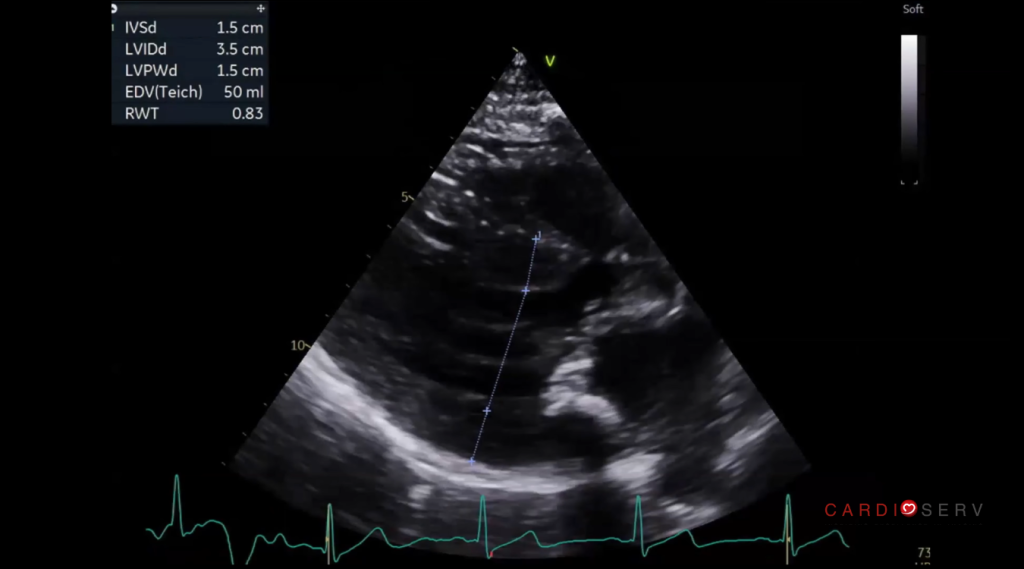

The Importance of Accurate Measurements

Once HCM is suspected, precision is critical. Even small errors, especially in wall thickness, can change how the study is interpreted.

Key considerations:

- Avoid including right ventricular structures in septal measurements

- Use multiple views (long and short axis)

- Identify the thickest segment, not just the basal septum

- Clearly document the pattern of hypertrophy

Probe position also matters. A slight shift in the intercostal space can improve alignment and help avoid RV inclusion.